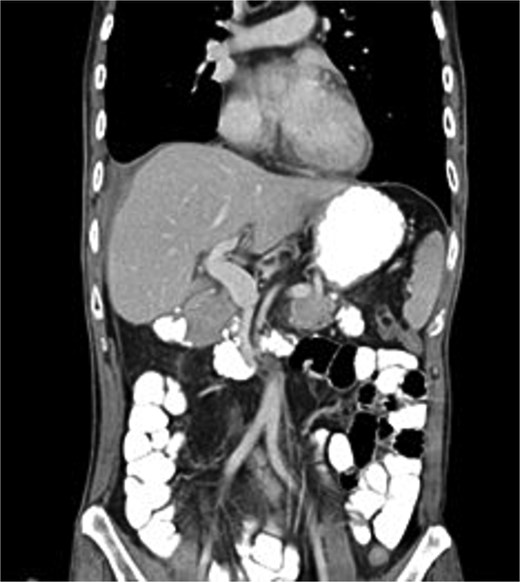

After stabilization in the surgical intensive care unit, a contrast-enhanced whole-body computed tomography (CT) scan (Fig. 3) on postoperative day 2 revealed no active bleeding or pancreatic parenchymal/ductal injury. On postoperative day 5, the patient underwent staged reconstruction. Intraoperative findings demonstrated extensive bile leakage from the anterior wall of the second portion of the duodenum, consistent with advanced erosion and friable tissue, which precluded the feasibility of a Roux-en-Y duodenojejunostomy. Reconstruction consisted of gastrojejunostomy and pyloroplasty, colonic anastomosis, and feeding jejunostomy. Postoperative care included total parenteral nutrition with gradual advancement to jejunostomy feeding. The patient subsequently developed a delayed liver laceration with intra-abdominal hematoma, traumatic pancreatitis, gastrojejunostomy leakage, and colonic anastomotic leak, all of which were managed conservatively. Nevertheless, the course was complicated by duodenal stump leakage with a high-output biliary fistula refractory to standard management, with drainage volumes reaching ~1000 ml/day.

CT scan showed no active bleeding or pancreatic parenchymal/ductal injury.